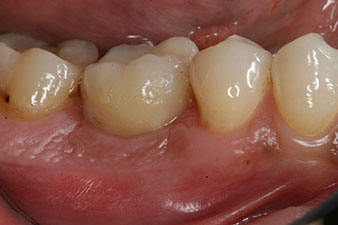

corona de composite

Figura 9: La corona de composite definitiva se adhirió en el laboratorio a un pilar híbrido PEEK, por lo que pudo atornillarse de inmediato.